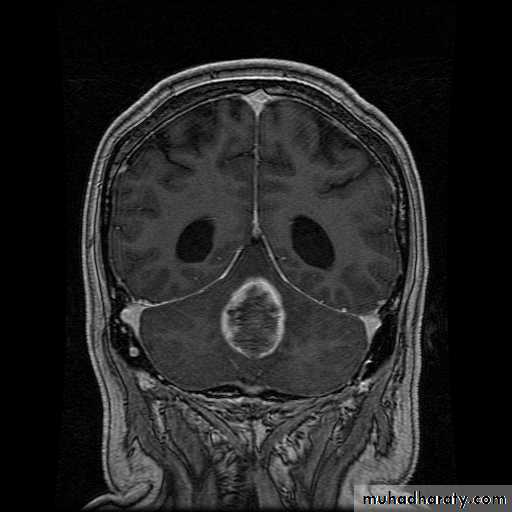

Ependymoma:

arise from the epidermal lining of the ventricular system, usually whitish in color & can lead to early hydrocephalusCT scan of all gliomas shows usually hyperdense lesion, irregular in shape, surrounded by edema & may be enhanced with or without cystic degeneration.

( CORONAL MRI )

Note: all gliomas are dealt with by surgical intervention ,by excision of the tumor followed by radiotherapy , but prognosis is not very good & fluctuates from 5 years survival of less than 5% in Glioblastoma multiformis to up to 100% 5 years survival in Oligodendroglioma treated by surgery & successive radiotherapy.